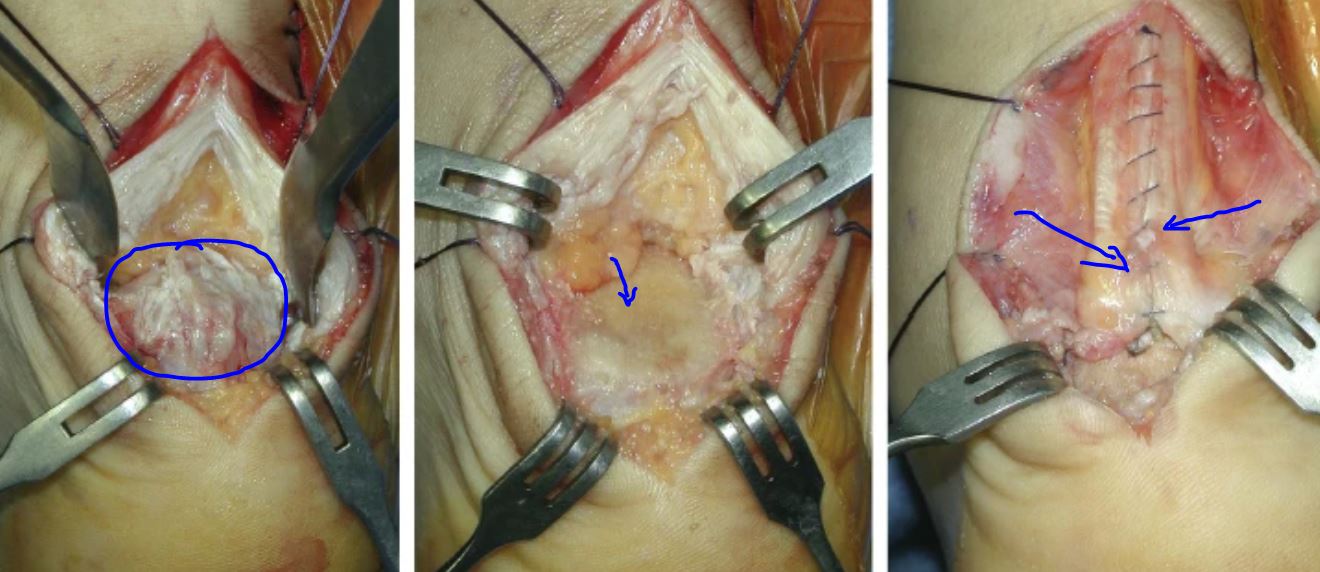

如果跟腱炎性引起肌腱撕裂超过50%以上的就应该手术治疗,缝合肌腱或做跟腱止点重建手术。

还有一种跟骨形态畸形:Haglund综合征—Haglund病是指跟骨后上部异常突起,跟骨后上方和跟腱之间的滑囊在反复的机械撞击下产生的炎性症状。 这种情况下保守治疗无效也应该手术治疗,磨除骨刺。

如果症状得不到缓解或加重,也可以选择在正规医院通过手术切除跟腱钙化部位,从而缓解此症状。手术中使用缝合锚重建跟腱止点,建议使用双排锚钉构建来增加强度。术后恢复性锻炼至少需要9个月。